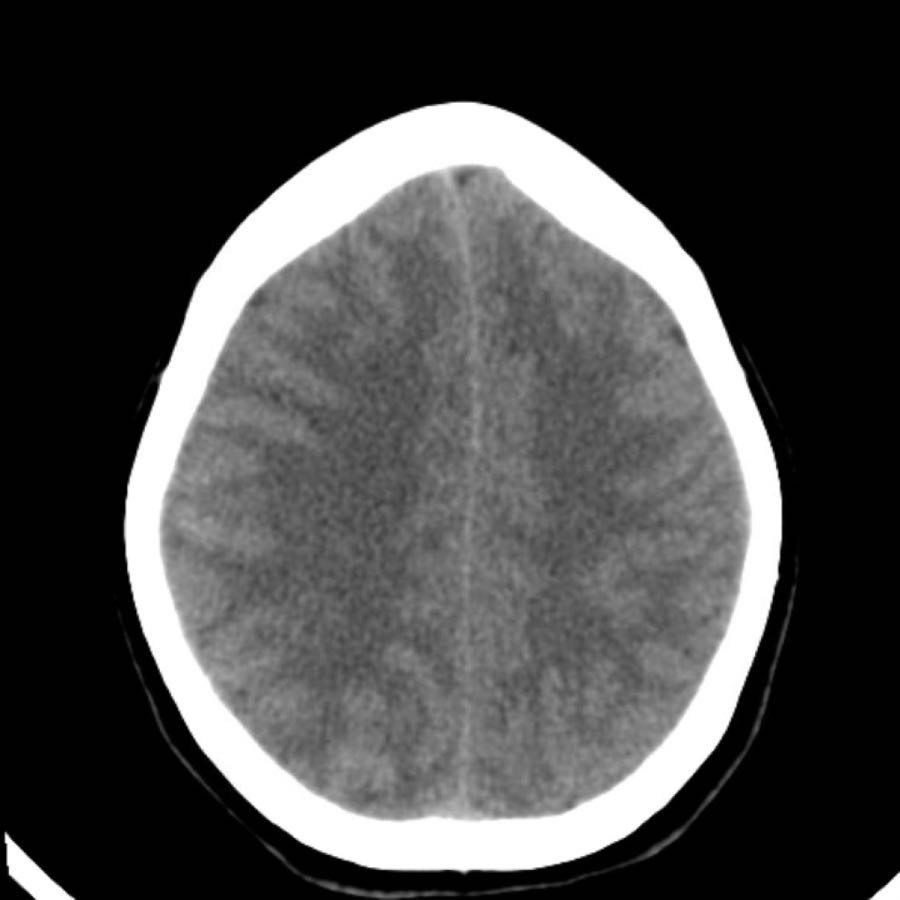

Xuất huyết do tăng huyết áp thường xảy ra ở bệnh nhân cao tuổi và thường ở vị trí trung tâm.

Điều này giúp phân biệt xuất huyết do tăng huyết áp với xuất huyết ở bệnh nhân mắc bệnh lý mạch máu não dạng bột (CAA) – vốn có vị trí ngoại vi hơn, mặc dù có thể có sự chồng lấp.

Các hình ảnh cho thấy xuất huyết do tăng huyết áp điển hình tại nhân bèo (putamen), là phần lớn nhất và nằm ngoài cùng của hạch nền.